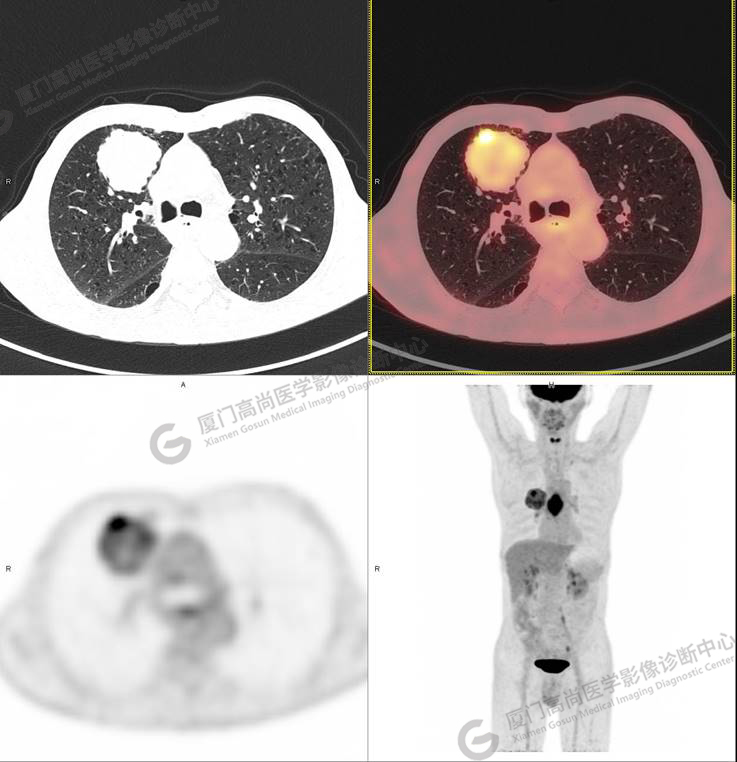

圖1

右肺上葉軟組織密度腫塊,大小約5.9×5.5×6.3cm,形態(tài)不規(guī)則,邊緣見棘突,其內(nèi)密度不均勻,放射性攝取不均勻性增高,SUVmax 6.46;腫塊周圍見多發(fā)小結(jié)節(jié)影,較大者直徑約0.6cm,放射性攝取未見明顯增高。影像學(xué)表現(xiàn)考慮右肺癌并肺內(nèi)轉(zhuǎn)移。